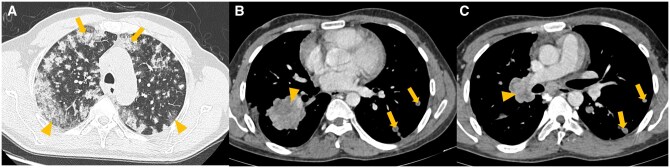

Abstract Image